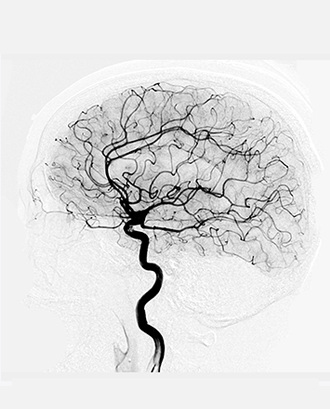

Cerebral Angiography (DSA)

(for Stroke/Subarachnoid haemorrhage/Moya-Moya Disease/ Vasculitis/AVM/Aneurysm/CVT etc.)

Cerebral angiography is a diagnostic procedure commonly done for the diagnosis and evaluation of various vascular lesions of the brain like aneurysm, arteriovenous malformation, dural-AVM, occlusion of the brain artery, collateral circulation in brain artery occlusion to dene need for the intervention etc.

This procedure is generally performed under local anaesthesia. A needle puncture is done in the groin to access the artery of the groin(femoral artery) and then cannulated with a back-lock femoral sheath. Through this femoral sheath a catheter (thin, long tube) is navigated through the aorta into the brain arteries (carotid and vertebral arteries). Subsequent to this a dye (radio-opaque, water soluble iodinated contrast) is injected in the brain artery to cine imaging is performed to obtain pictures in various planes using advanced neurovascular cathlab. These images are then carefully analysed and if needed then three dimensional rotating angiograms can be performed in a few seconds time to obtain a very clear high resolution image which can pick up even micro aneurysm of 1mm in size.

Cerebral angiography (DSA) is generally a day-care procedure in which a patient arrives at the hospital on a scheduled day in an overnight fasting state and after initial clinical assessment and preparation including consent for the procedure, the patient is shifted to the Stroke and Interventional Cathlab. After the procedure the catheter is removed and the puncture site is given manual compression for a few minutes to stop bleeding from the punctured femoral artery. The patient is then shifted to the ICU/Day-care for monitoring and after 6 hours of the procedure, the patient is generally discharged to the home.